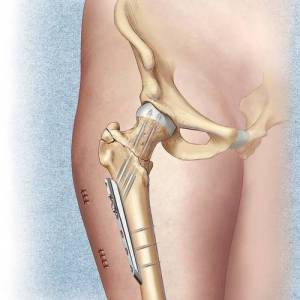

- Травмы верхнего конца бедра. Если произошел перелом верхнего конца кости, метод остеосинтеза не применяется при вколоченных повреждениях шейки бедра. В остальных ситуациях, если позволяют жизненные показания, можно лечить пациента оперативным путем. Часто именно благодаря такому методу можно спасти жизнь пациенту, сократить срок его реабилитации и достичь быстрого сращения перелома. В основном в ходе операции применяются канюлированные винты, г-образная пластина и трехлопастный гвоздь. Остеосинтез выполняется на 2-4 сутки после травмы. Сначала применяют скелетное вытяжение, пациент подготавливается к операции и делается контрольный снимок с помощью рентгена. Целью операции является точное сопоставление костных отломков и их последующая фиксация. Если произошел серединный перелом бедренной шейки, во время операции используется трехлопастный гвоздь.

Перелом бедренного диафиза. В этом случае остеосинтез – главный метод лечения. Консервативный путь выбирается только тогда, когда невозможно использовать хирургическое вмешательство. Операций при переломе диафиза выполняется на 5-7 сутки после травмы. Перед этим накладывается скелетное вытяжение. Во время остеосинтеза применяются пластины, стержни и аппараты для внешней фиксации. Срочную операцию нельзя проводить при тяжелом состоянии пациента. Необходимо сначала нормализовать его состояние. Если перелом оскольчатый или наблюдаются сочетанные травмы, может возникнуть необходимость в срочном обездвиживании отломков, чтобы прекратить последующее травмирование бедренных тканей, так как это может плохо сказаться на состоянии пациента.

- Травмы нижнего участка бедра. Остеосинтез используется при изолированных переломах бедренных мыщелков. В ходе операции вскрывается место перелома, а отломанный мыщелковый фрагмент фиксируется с помощью винтов. Иногда используют аппараты для осуществления чрескожной фиксации.

Врачи отмечают, что остеосинтез бедра является важной хирургической процедурой, применяемой при различных травмах и заболеваниях. Существует несколько видов остеосинтеза, включая внутренний и внешний. Внутренний остеосинтез подразумевает использование металлических пластин, винтов или стержней, которые фиксируют кости изнутри. Внешний остеосинтез, в свою очередь, включает применение аппаратов, которые крепятся снаружи и обеспечивают стабильность фрагментов кости.